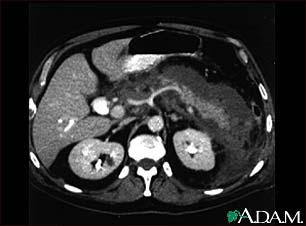

Pancreatitis, acute - CT scan

This upper abdominal CT scan shows inflammation and swelling of the pancreas caused by acute infection (pancreatitis).